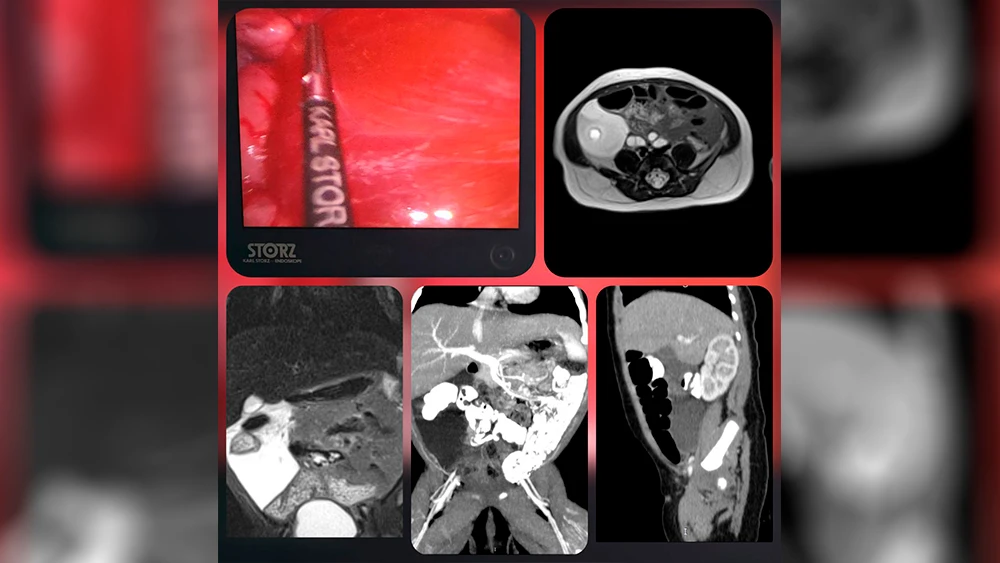

Ребенок был экстренно госпитализирован в отделение хирургии детей раннего возраста с крупным образованием в брюшной полости, обнаруженным на УЗИ. Консилиум врачей принял решение о проведении срочной операции.

Хирурги Мария Зыкова и Буй Вьет Анх выполнили малоинвазивную лапароскопическую операцию по удалению лимфатической мальформации с сохранением сосудов брыжейки. Для предотвращения рецидива внутреннюю поверхность кист обработали специальным полимерным раствором, препятствующим образованию лимфы.